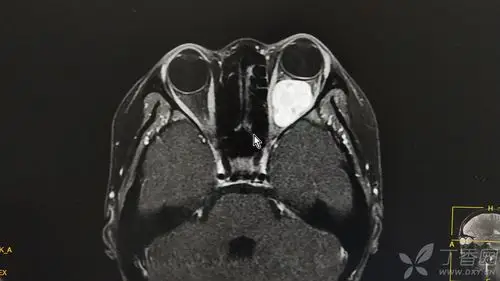

眼眶肿瘤 - 眼科专业讨论版 -丁香园论坛

眼眶肿瘤摘除术年龄不是障碍,全身评估后能够接受全麻是关键.